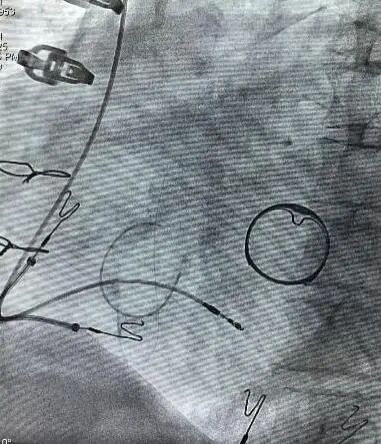

图4 术中阳极环测试,起搏阈值0.8V/0.4ms;提示电极植入深度大于等于11mm。